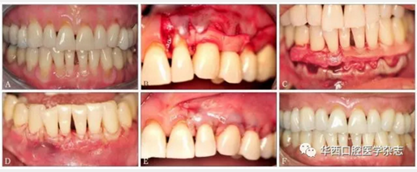

盡管使用ADM進行膜齦手術(shù)的長期療效一直存在爭議,但目前該技術(shù)仍是除游離結(jié)締組織外的另一個療效較為可靠的根面覆蓋手術(shù)(圖1)。

A:患者有廣泛性牙齦進行性退縮,牙根暴露、敏感,臨床附著水平喪失,附著齦喪失;B、C:手術(shù)采用半厚瓣,翻過膜齦聯(lián)合線,常規(guī)根面處理,采用5-0可吸收線用連續(xù)褥式縫合方式將ADM縫合在唇頰側(cè);D、E:無張力情況下,采用5-0可吸收線行連續(xù)褥式縫合,半厚瓣冠向復位將ADM完全覆蓋;F:術(shù)后20個月,由于大量牙槽骨吸收,牙根表面沒有達到完全覆蓋,但是角化組織(附著齦)增加了3~4 mm。

圖 1 ADM結(jié)合冠向復位瓣手術(shù)